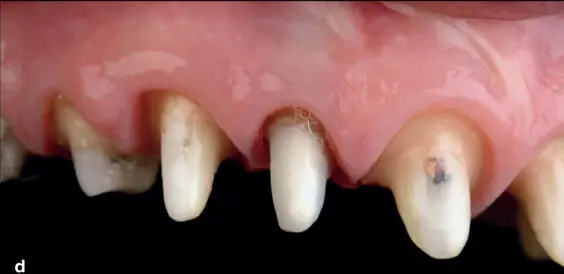

Fig 1-26 Orthodontic extrusion can be used to establish an optimal ferrule height, biologic width space, and an ideal gingival architecture. (a and b) During previous treatment, the endodontically treated maxillary right lateral incisor had insufficient ferrule height, and the restorative margin was placed in violation of the biologic width. (c and d) Orthodontic brackets were placed on the provisional restorations, and the maxillary lateral incisor was extruded to attain a ferrule dimension of 1.5 mm and to establish a biologic width of 3 mm. The more rapid the movement, the less likely it is to extrude the supporting structures. (e) Note the healthy biologic framework achieved by attaining a restorative dimension of 4.5 mm of supracrestal tooth structure. For more information, see chapter 2, Case 1.